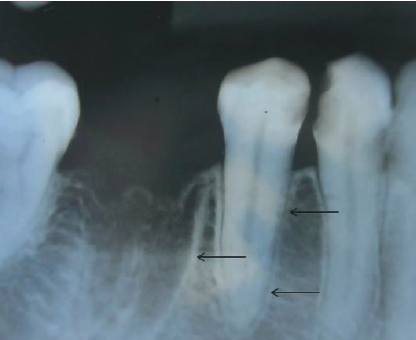

72. What is showing by arrow?

> Periodontal ligament (PDL) • Radiographically seen as a radiolucent line on inside of lamina dura PDL is thinner in the middle of the root and slightly wider near the alveolar crest and root apex average width: 0.5 mm). Position in relation to tooth can determine if lesion is attached to tooth structure (inside PDL) or not (outside PDL). Widening of the periodontal ligament space: Increased width of periodontal ligament space due to inflammation. Etiology: pulp necrosis, root fracture, trauma from occlusion, malignancies, scleroderma (generalized PDL)